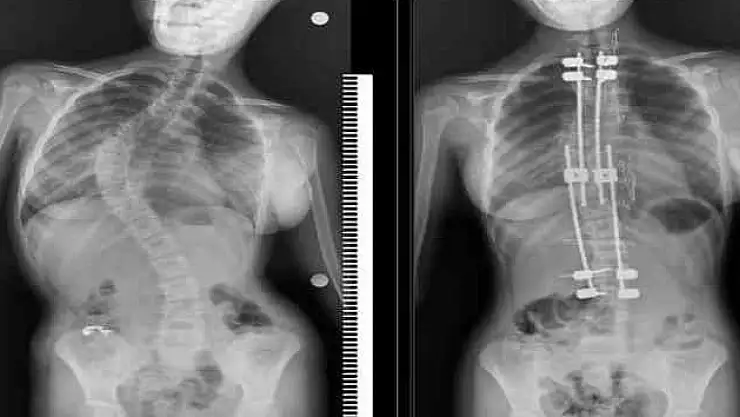

İleri derecede eğriliklerde cerrahinin bir seçenek olarak gündeme gelebileceğini söyleyen Üçpunar, ameliyat sonrası yaşamla ilgili endişelerin abartıldığını belirterek şunları kaydetti:

“Güncel bilimsel veriler, skolyoz cerrahisi geçiren çocukların yaşam kalitesinin sağlıklı yaşıtlarıyla neredeyse aynı olduğunu gösteriyor. Modern teknikler sayesinde bu hastalar eğitimlerine dönebiliyor, meslek sahibi olabiliyor ve sosyal yaşamda aktif yer alabiliyor. Cerrahi, bu sürecin sonu değil; pek çok çocuk için yeni bir başlangıçtır.”